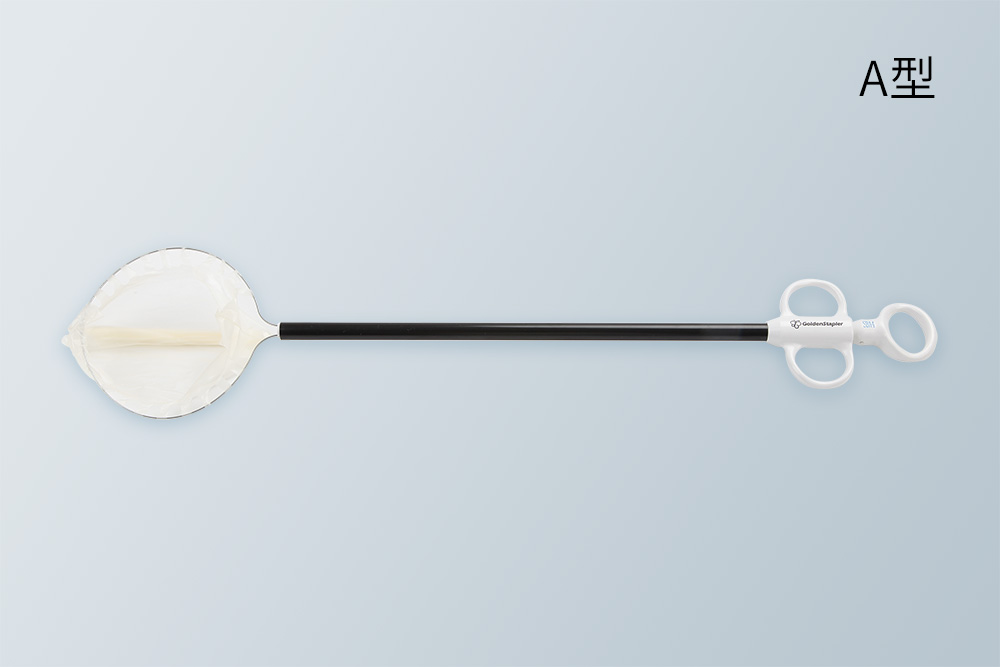

健瑞宝标本取出袋可用于胸或腹腔镜手术中,在胸或腹腔内盛装切除的标本并将此标本取出。产品采用柔软超强材质,抗爆破压高,防止漏液。有两种不同款式,按需选用,灵活方便。产品有多种规格及尺寸,适合于手术切除的不同尺寸标本。

健瑞宝标本取出袋可用于胸或腹腔镜手术中,在胸或腹腔内盛装切除的标本并将此标本取出。产品采用柔软超强材质,抗爆破压高,防止漏液。有两种不同款式,按需选用,灵活方便。产品有多种规格及尺寸,适合于手术切除的不同尺寸标本。

● 柔软环形钢丝设计,自动张口,以便装入标本

● 随意放入胸腔或腹腔,取标本方便

● 超强材料制成标本袋,抗拉抗内爆破压,防止漏液

● 柔软涂层尼龙袋,袋口抗拉强度大

柔软钢丝袋口 柔软环形钢丝设计,自动张口,以便装入标本

超强材质 超强材料制成标本袋,抗拉抗内爆破压

柔软涂层尼龙袋 柔软涂层尼龙袋,袋口抗拉强度大

抗爆破压高 袋内抗爆破压高,防止漏液

灵活方便 随意放入胸腔或腹腔,取标本方便